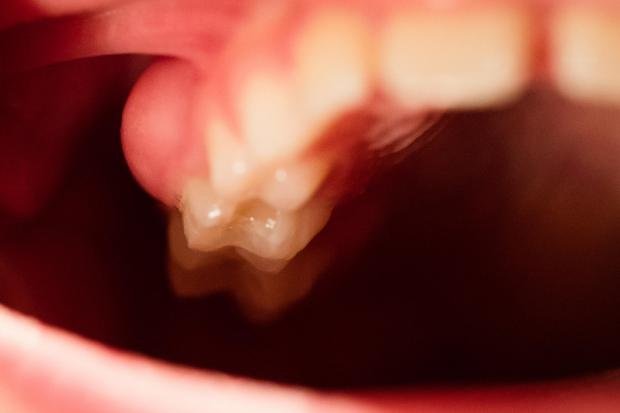

Bakteriler, dişin sert dış tabakasında oluşan diş çürüğü veya çürüklerin neden olduğu küçük deliklerden dişe girer. Çürükler sonunda minenin altındaki dentin adı verilen daha yumuşak doku tabakasını parçalar. Çürük devam ederse, delik sonunda dişin yumuşak iç pulpasına nüfuz eder ve enfekte olur.

Bu durum pulpitis olarak bilinir. Pulpitis ilerledikçe, bakteriler dişi çevreleyen ve destekleyen alveolar kemik adı verilen kemiğe doğru yol alır ve periapikal apse oluşur.